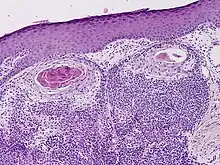

Hidradenocarcinoma

Hidradenocarcinoma (also known as malignant hidradenoma, malignant acrospiroma, clear cell eccrine carcinoma, or primary mucoepidermoid cutaneous carcinoma) is a malignant adnexal tumor of the sweat gland. It is the malignant variant of the benign hidradenoma. It may develop de novo or in association with an existent hidradenoma.[1]